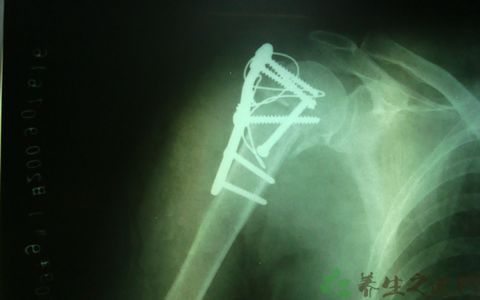

②治疗骨折基本可分为钢板螺丝钉和髓内针内固定两大系统,所以临床治疗也一直沿用着普通接骨板、桥型板、骨外钢板固定及石膏或夹板等技术,这些技术对3度以上的粉碎性骨折治疗则束手无策,均不能使散碎的骨折片复位。

③在身体及经济条件允许情况下可考虑行切开复位内固定手术,选择合适的时机,手术后可较早活动肢体,进行功能恢复,预后较好。